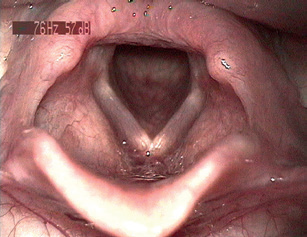

Laryngoskopické vyšetření hrtanu

V otorinolaryngologii máme výhodu možnosti laryngoskopického vyšetření hrtanu. Vchod do hrtanu a vchod do jícnu jsou anatomicky velmi blízko, proto můžeme na sliznici hrtanu u nemocných s EERCH pozorovat četné slizniční změny (obr. 2). Slizniční změny hrtanu, které jsou charakteristické pro mimojícnové projevy refluxní choroby jícnu, byly popsány (Belafsky 2001) a jsou dobrým vodítkem k diagnostice EERCH. K usnadnění hodnocení slizničních změn na sliznici hrtanu je možné použít nástroj Reflux Finding Score (RFS) (tab. 5).